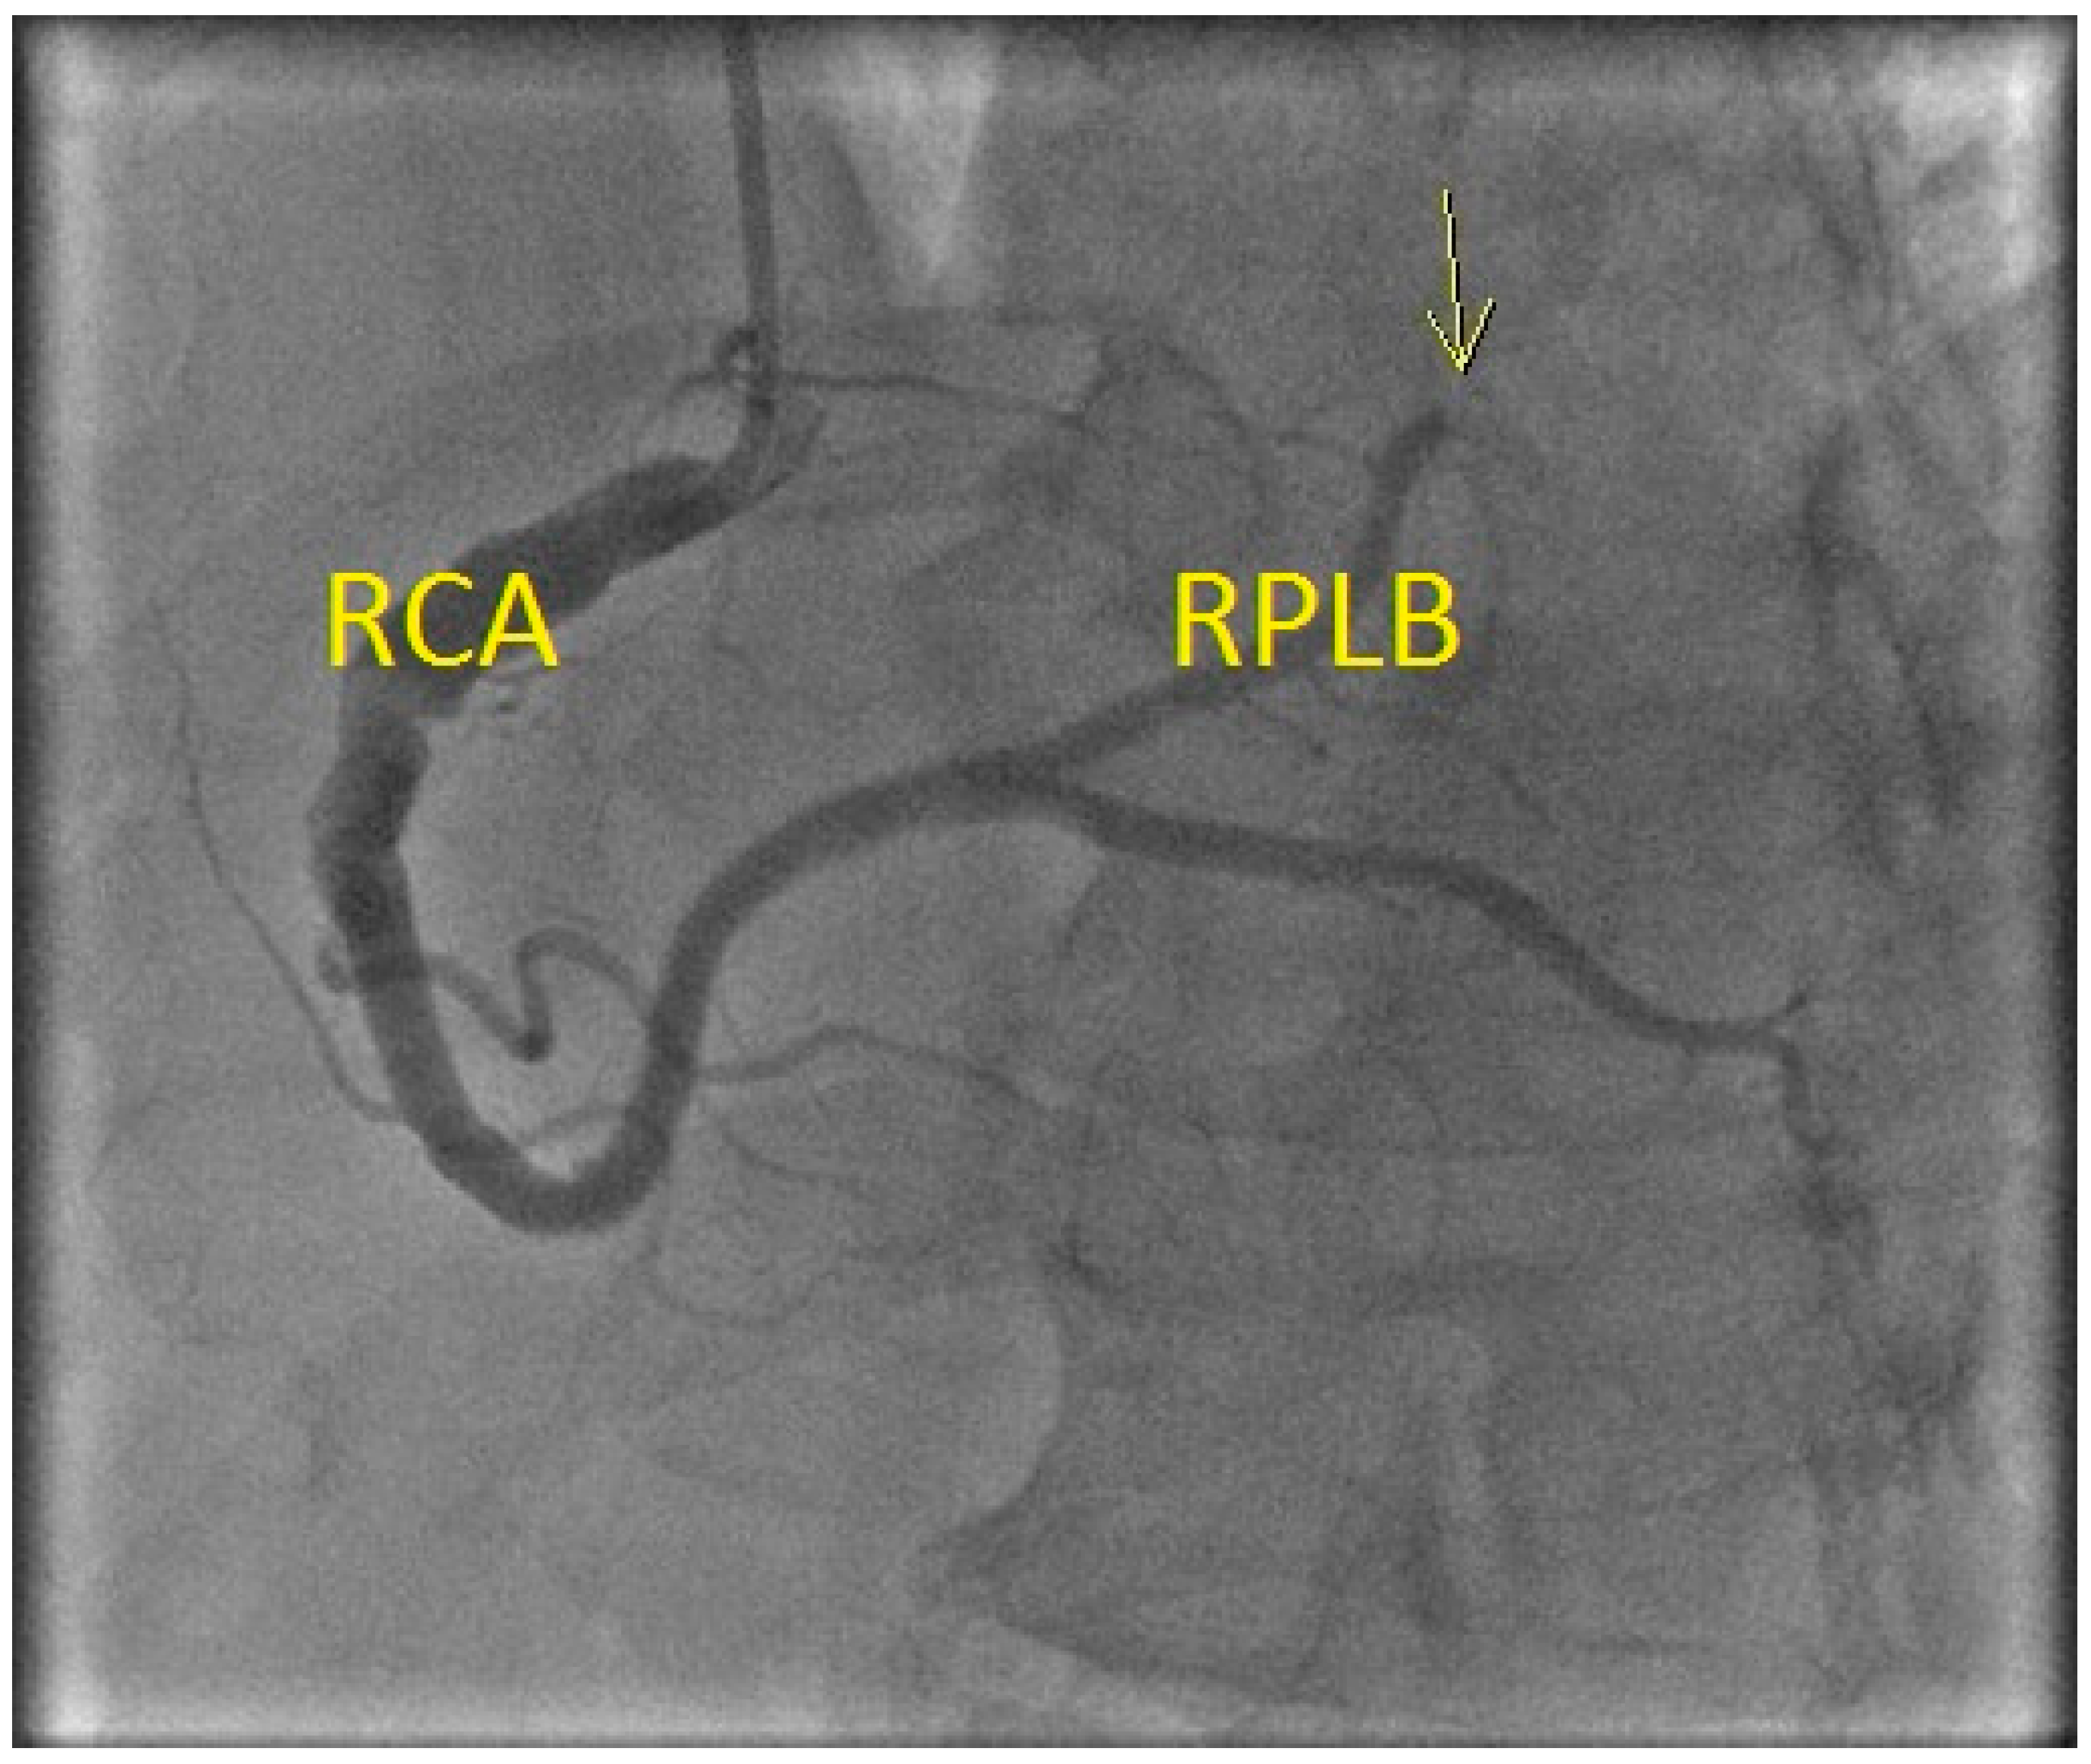

Figure 3.

Coronary angiogram showing thrombus at the proximal right coronary artery (RCA) with occlusion (yellow arrow) of the distal right posterolateral branch (RPLB).